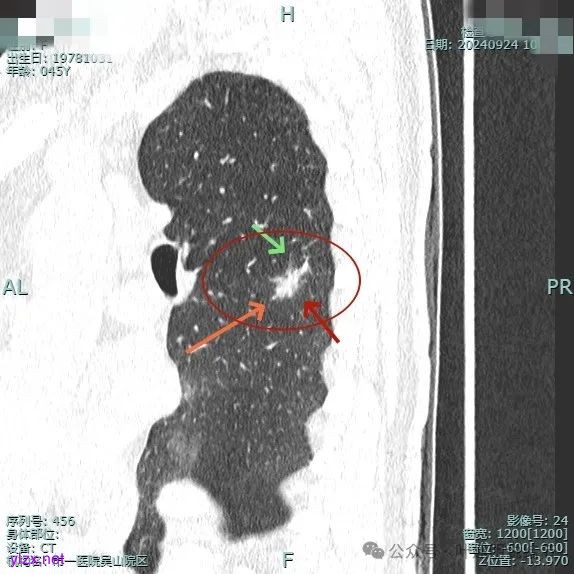

我们先来看2024年9月时的影像:

病灶2:

右中叶内侧段可见混合密度结节,大部分实性,形态与下叶背段的类似。

病灶1:

病灶是混合密度,边缘少许淡磨玻璃,灶内不太致密,表面不平,血管征有,但说不上明显异常增粗。

病灶紧贴叶间裂,而且感觉跨过肺叶,部分影响到上叶了,病灶本身密度虽实性为主,但是不太致密,有点松散的感觉。

总体实性部分密度较高,而磨玻璃部分密度较低,且瘤肺边界欠清,关键是跨叶间裂生长,这与肿瘤似乎不容易解释些。

毛刺有但不太锐利,磨玻璃有但偏淡,实性为但不太致密,叶间裂与之关系密切,病灶跨叶生长。

上图显得与肿瘤较为符合,但跨叶生长的话,侵袭力应该较强,可她这病灶较刚发现时进展并不太明显。

上图层面也较符合恶性,血管进入明显,有浅分叶的样子,整体觉得有一定收缩力与膨胀感。

病灶表面不平,混合密度,磨玻璃成分较淡。